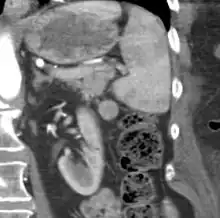

| CT scan of an accessory spleen (circular object in center of image) between the spleen and left kidney. | |

An accessory spleen is a small nodule of splenic tissue found apart from the main body of the spleen. Accessory spleens are found in approximately 10 percent of the population[1] and are typically around 1 centimetre in diameter. They may resemble a lymph node or a small spleen. They form either by the result of developmental anomalies or trauma.[2] They are medically significant in that they may result in interpretation errors in diagnostic imaging[2] or continued symptoms after therapeutic splenectomy.[1] Polysplenia is the presence of multiple accessory spleens rather than one normal spleen.

Accessory spleens may be formed during embryonic development when some of the cells from the developing spleen are deposited along the path from the midline, where the spleen forms, over to its final location on the left side of the abdomen by the 9th–11th ribs. The most common locations for accessory spleens are the hilum of the spleen and adjacent to the tail of the pancreas. They may be found anywhere along the splenic vessels, in the gastrosplenic ligament, the splenorenal ligament, the walls of the stomach or intestines,[3][4] the pancreatic tail,[5][6] the greater omentum,[7][8] the mesentery,[9] the renal fossa,[10][11] or the gonads and their path of descent.[12] The typical size is approximately 1 centimeter, but sizes ranging from a few millimeters up to 2–3 centimeters are not uncommon.[2]

If splenectomy is performed for conditions in which blood cells are sequestered in the spleen, failure to remove accessory spleens may result in the failure of the condition to resolve.[1] During medical imaging, accessory spleens may be confused for enlarged lymph nodes or neoplastic growth in the tail of the pancreas,[5] gastrointestinal tract, adrenal glands or gonads.[2]